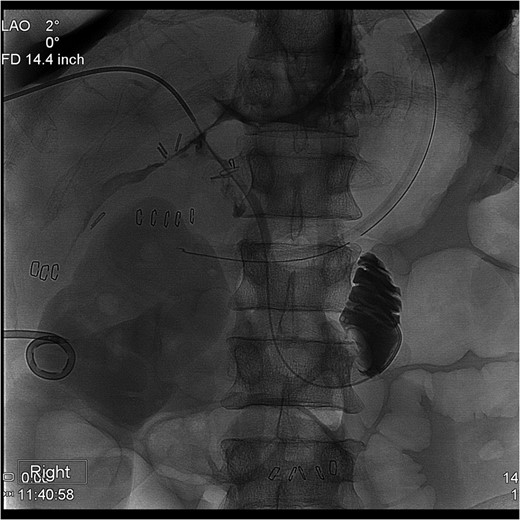

The PTC study confirmed the presence of a completely transected duct, and, fortunately, the ductal injury was traversed with a wire with entry into the distal ductal orifice and into the duodenum (Figs 4–6). Following the procedure, the patient was taken directly to the operating room for open surgical repair.

Percutaneous Transhepatic Cholangiogram with wire traversing into the distal common bile duct orifice. Note duodenum filling with contrast.